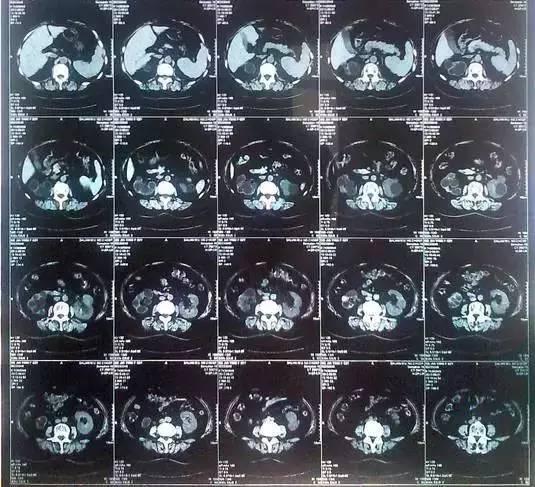

55歲的老何是金華東陽(yáng)市橫店鎮(zhèn)人,一名普通工人。因?yàn)轭l繁腰疼去醫(yī)院檢查,結(jié)果CT顯示,他的左腎里竟然密密麻麻布滿(mǎn)了石頭,幾乎把整個(gè)腎都塞滿(mǎn)了,手術(shù)從左腎取出了420顆結(jié)石!

醫(yī)生看了CT的結(jié)果顯示,非常嚴(yán)肅的告訴他,他的左腎已經(jīng)被結(jié)石占滿(mǎn),必須馬上手術(shù)治療。這次手術(shù)讓主刀醫(yī)生觸目驚心,他們居然從老何的左腎取出了420顆結(jié)石。這是他們手術(shù)生涯上從來(lái)沒(méi)有遇到過(guò)的病例。